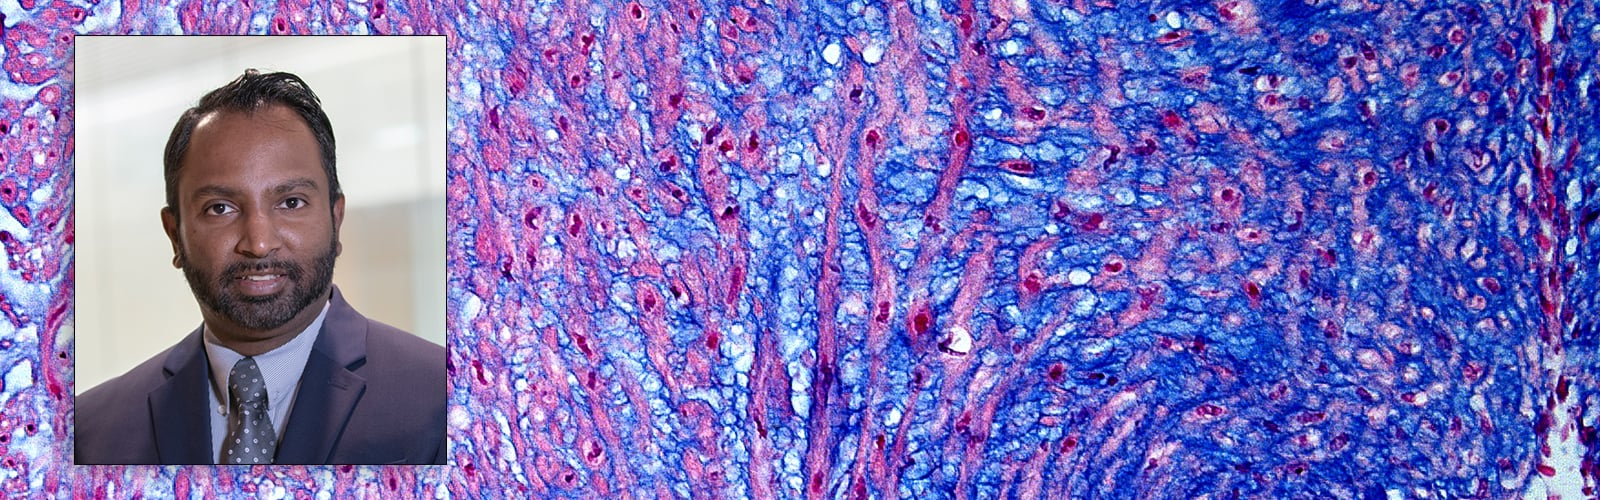

Nandadasa Primary Cilia and Extracellular Matrix Lab

The research in the Nandadasa laboratory is focused on understanding the function of extracellular matrix proteases belonging to the ADAMTS family of metalloproteinases in embryonic development and in disease. Specifically, we investigate a group of developmental birth defects known as ciliopathies that arise by the dysgenesis of the primary cilium, a crucial antenna-like cellular organelle, present in nearly all cells. ADAMTS proteases (A disintegrin and metalloproteinase with thrombospondin type 1 motifs), are secreted molecules mainly known to act on the extracellular matrix. In paradigm-shifting discoveries we have shown that ADAMTS9 and ADAMTS20 are endocytosed and recycled to the ciliary vesicle in Rab11+ vesicles and that they play crucial proteolytic functions leading to primary cilia formation. ADAMTS9 mutations cause nephronophthisis (NPHP) and Joubert syndrome (JBTS), two devastating ciliopathies which are diagnosed in young children and infants.  Adamts9 and Adamts20 mutant mice available to us manifest severe embryonic defects resembling human ciliopathies and provide valuable disease models. The goals of our research are to: